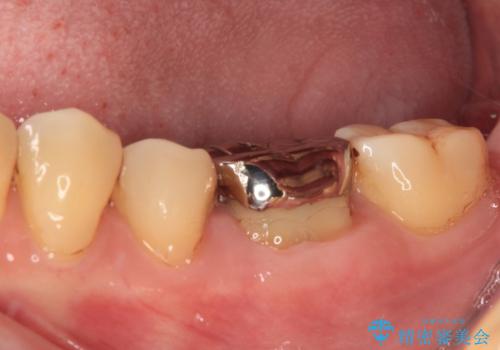

- 人と話す際に、下顎の奥にある銀歯が目立って気になるとのことで来院された患者様です。

左右の奥歯に銀歯のクラウンが装着されていたため、銀歯除去後に仮歯に置き換え、フルジルコニアクラウンにて補綴治療を行うこととしました。